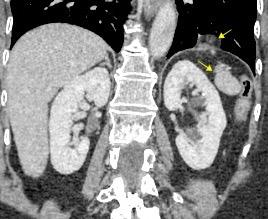

Riñones poliquísticos

Elevación bilateral por riñones poliquísticos. Hernia hiatal ¡Sin gas en abdomen!